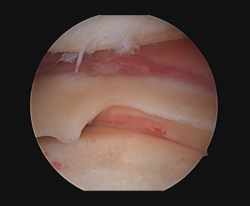

Meniscal root lesions

Meniscal root lesions are lesions located at less than 1 cm from the bone insertion of the meniscus, or lesions that involve bone avulsion of the anchoring zone (Figure 4). While lesions of the posterior root of the medial meniscus are related to degenerative processes, lesions of the posterior root of the external meniscus are associated to lesions of the ACL (7-12%)(30). Rupture of the posterior root of the medial meniscus biomechanically behaves like a total meniscectomy(31), while rupture of the posterior root of the external meniscus associated to ACL rupture results in an increase in anterior translation of the tibia and adds increased rotational instability, incrementing pivot shift(32).

Figure 4. Rupture of the posterior root of the medial meniscus. Note the lack of continuity in the posterior horn of the medial meniscus, exhibiting a space between the root and its insertion imprint in the tibia (*). Left knee; view from the anterolateral port.